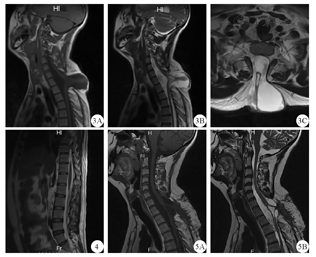

患者男性,28岁,因"发热3 d,意识模糊1 d"于2019年4月6日入院。3 d前患者无明显原因突然发热,体温37.5~38.8 ℃,就诊于当地医院,服用"氨咖黄敏胶囊、阿莫西林胶囊"等药物治疗,发热无缓解。1 d前患者逐渐出现反应迟钝、睡眠增多、意识模糊,并逐渐加重,以"中枢神经系统感染查因"收入神经内科。患者否认有鼻塞、流涕、咽痛、咳嗽、腹痛、腹泻等呼吸系统及消化系统感染病史。入院体检:体温38.5 ℃,心率98次/min,呼吸21次/min,血压126/80 mmHg(1 mmHg=0.133 kPa)。后颈部正中处有一5 cm×6 cm大小包块,局部皮肤发红、破溃,皮温较高,触之有波动感(图1)。神经专科检查:意识模糊,精神差,答非所问,高级智能异常,四肢肌力、肌张力正常,四肢腱反射正常,双侧病理征阴性,颈强直,颌距胸4横指,双侧克尼格征(+),双侧布鲁斯基津征(+)。辅助检查:血常规:白细胞16.78×109/L,中性粒细胞计数15.48×109/L;降钙素原19.75 ng/mL;腰椎穿刺示颅内压320 mmHg;脑脊液常规:外观呈黄色,浑浊,潘氏试验阳性,白细胞8120×106/L,多核为主;脑脊液生化:蛋白3163.5 mg/L,葡萄糖0.04 mmol/L,氯115.8 mmol/L;肝肾功、凝血功能、电解质、风湿免疫等检测项目均正常,脑脊液及血细菌培养未发现致病菌;头颅MRI未见明显异常,脑室无扩大(图2);颈胸椎MRI示C7、T1、T2棘突缺如,脑脊液囊向后突出,到达皮肤表层,脊髓神经根和脊膜等组织疝出,脊髓软化或脊髓空洞形成,脊髓神经根从背侧延伸至脊膜壁(图3);腰椎MRI示L4/5、L5/S1椎间盘突出,圆锥位置未下降,脊髓、马尾及终丝未见到明显牵拉(图4)。诊断:细菌性脑膜炎;颈胸段脊髓脊膜膨出。

3A:矢状位T1WI像,3B:矢状位T2WI像,3C:横断位T2WI像;5A:矢状位T1WI像,5B:矢状位T2WI像

治疗经过:给予万古霉素静脉滴注(1 g、1次/每12小时)联合美罗培南静脉滴注(2 g、1次/每8小时)、甘露醇静脉滴注(25 g、1次/每8小时),次日患者神智转清。应用4周后患者体温逐步恢复正常,反复多次复查脑脊液示结果正常后随即停用。于发病后2个月予患者全麻下脊髓及神经根松解术+脊膜膨出修补术:采用气管插管全身麻醉,俯卧位,调低患者头部,降低脑脊液外漏的可能性。取梭型切口,首先暴露硬脊膜,切除多余畸形的棘突、椎板以及硬脊膜内外脂肪和纤维结缔组织,在内镜下松解膨出的神经纤维组织,沿蛛网膜边缘游离,仔细彻底分离、松解粘附在囊壁上的脊髓及神经根,之后还纳于椎管内,最后切除膨出的多余硬脊膜,用自身筋膜缝合硬脊膜,将皮肤逐层对位缝合。术中采用双极电刺激器刺激患者正中神经,在头顶端的C3与C4位置处对头皮躯体感觉诱发电位(SEP)进行记录;运动诱发电位(MEP)的监测是通过对C1与C2进行刺激,在上肢的大鱼际进行记录;均持续在手术阶段中进行监测并记录。术中对不确定是否会导致功能障碍的组织结构,利用双极电刺激器直接通过电刺激对诱发的肌电图(EMG)进行记录,来确定神经根位置与脊髓位置以及病变间的解剖关系,以防止误伤。SEP以波幅降低50%、潜伏期延长10%作为报警标准,MEP以波幅消失作为报警标准,诱发EMG以探针刺激时出现肌电爆发来确认神经组织。术后患者颈椎MRI复查示脊髓中央管较前稍扩张,脊髓神经根与脊膜部分相连(图5)。术后随访6个月,患者活动自如,无任何临床不适。